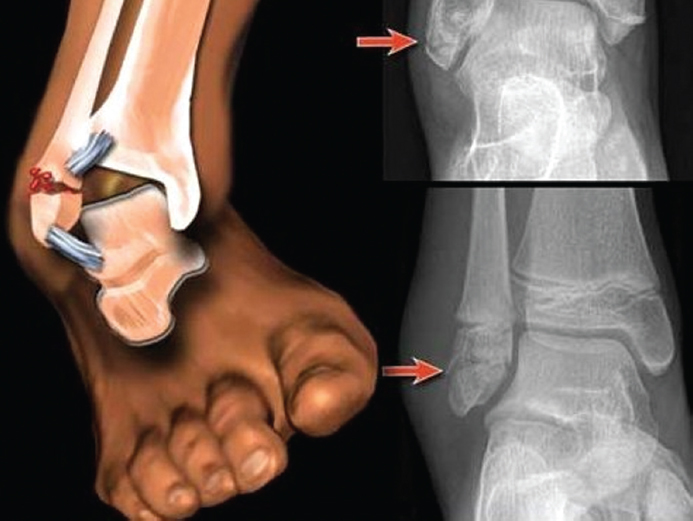

Патологический перелом, причиной которого является предсуществующий патологический процесс в кости, например остеопороз. Он возникает в той области кости, которая уже поражена каким-либо патологическим процессом и её прочность значительно снижена (рис. 26).

Рис. 26. Патологический перелом лодыжки при остеопорозе / Fig. 26. Pathological ankle fracture in osteoporosis

Такой перелом возникает спонтанно или при небольшой травме. Заживление патологического перелома происходит очень медленно и зависит от тяжести основного заболевания.